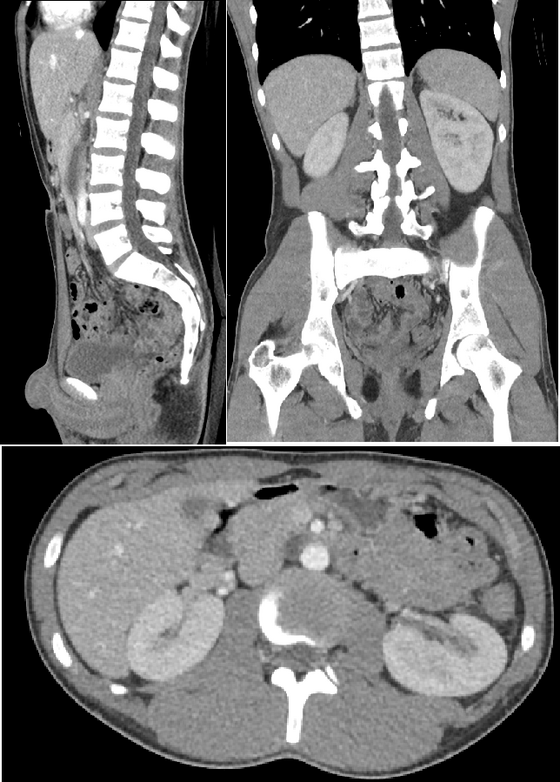

Body CT (CAT Scan)

Computed tomography (CT) of the body uses sophisticated x-ray technology to help detect a variety of diseases and conditions. CT scanning is fast, painless, noninvasive and accurate. In emergency cases, it can reveal internal injuries and bleeding quickly enough to help save lives.

CT images of internal organs, bones, soft tissue and blood vessels provide greater detail than traditional x-rays, particularly of soft tissues and blood vessels.

Using specialized equipment and expertise to create and interpret CT scans of the body, radiologists can more easily diagnose problems such as cancer, cardiovascular disease, infectious disease, appendicitis, trauma and musculoskeletal disorders.